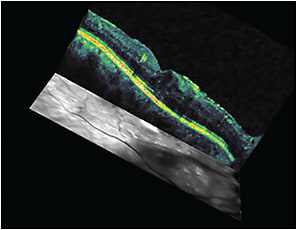

Figure 2. Three-dimensional OCT map of DME before treatment.

OCT can be ordered again after 18 weeks based on treatment plan (Figures 3 and 4), to monitor the effectiveness of treatment. Further, it can help us decide whether it is mandatory to change, stop, or continue with the treatment plan.

Figure 3. The same patient as in Figures 1 and 2, following four anti-VEGF injections.

Figure 4. Three-dimensional OCT map for the patient in Figures 1, 2, and 3, after four anti-VEGF injections.